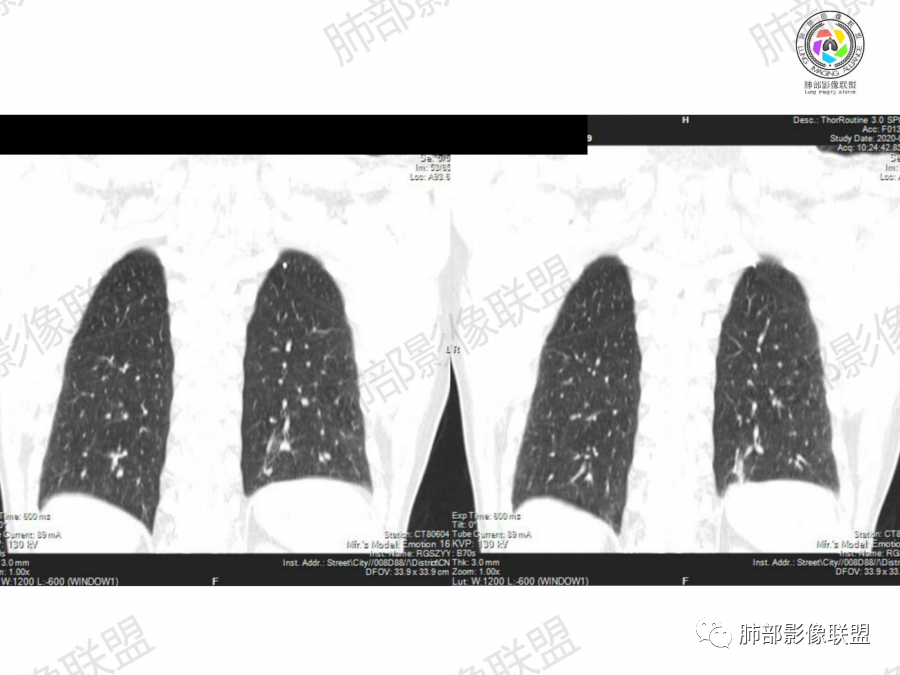

晨读:左肺下叶胸膜下实性结节影边缘毛糙,有毛刺,分叶,近段支气管未见显示,可能堵塞,远端宽基底与胸膜相贴,边缘平直,部分彭隆,病灶局限、单发,无增强,不好判断肿瘤血供,临床男性,63岁,无症状,体检发现,有吸烟史,考虑恶性:腺癌,鳞癌,小细胞肺癌,鉴别:肺隐球菌建议增强及穿刺检查。

老年男性,吸烟史。左下肺外周结节,糊墙,部分边缘平直、部分膀隆,见分叶,支气管截断?部分边缘似乎有GGO,内部情况不详。整体考虑恶性,腺癌可能性大,注意鉴别鳞癌、炎性肉芽肿。

老年男性,左肺下叶胸膜下团块,有膨隆有收缩,局部细支气管似截断,边缘少许毛刺,重建整体平直收缩为主,胸膜糊墙,首先考虑炎性肉芽肿,长期吸烟史,又是老年男性,肿瘤是必须警惕的,常规治疗后复查。

老年男性,左肺下叶近胸膜下结节,边缘收缩平直为主,胸膜糊墙,支气管显示不清,病灶密度均匀,首选考虑炎性肉芽肿,鉴别肺癌。

晨读病例,老年人 ,吸烟史,左肺下叶结节影,密度均匀,边缘毛糙,周围可见长毛刺,病灶边缘分叶,局部膨隆,部分边界平直,收缩,病灶相邻胸膜处可见糊墙征象,病灶近肺门处见支气管堵塞,考虑恶性病变,周围型肺癌:鳞癌伴肺不张>腺癌,鉴别隐球,炎性假瘤。

1、老年男性,大量吸烟史,无症状,体检左下肺孤立结节。

2、影像表现:无肺气肿背景、定位左肺下叶后基底段,不规则结节、与支气管关系不明确,部分边缘平直、部分膨隆,病变与胸膜宽基底相连,病变与胸膜糊墙征,病变周围见细、长、软毛刺,病变密度比较均匀。影像总体倾向炎症、符合肺组织慢性炎症伴机化。